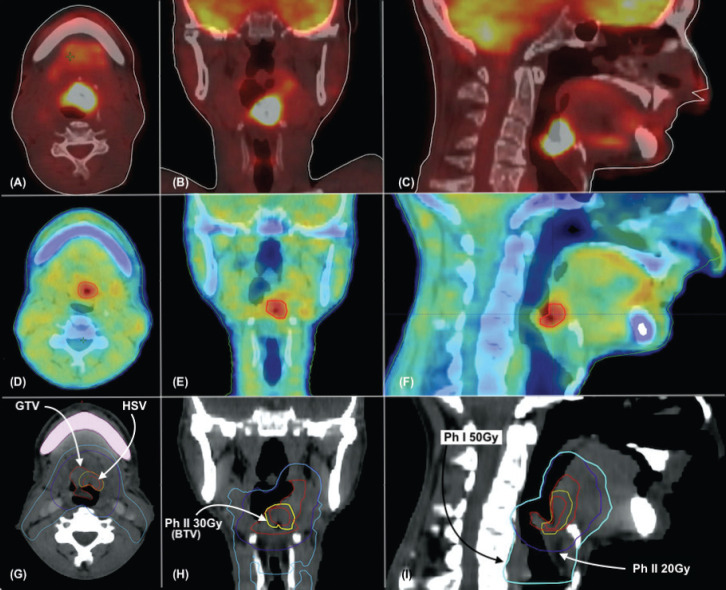

Methods: The dose-escalated hypoxia-adjusted radiotherapy trial is an open-label, parallel, randomised, single-centre, phase II study. Patients with HNC will undergo [18F]. FMISO PET CT to identify hypoxic regions. Normoxic patients will be labeled as Arm 1 and will not be part of the primary assessment. Patients with hypoxia will be stratified into two arms (2 and 3). Arm 2 will receive standard radiotherapy of 70 Gy in 2 Gy fractions, while Arm 3 will receive an additional boost to the hypoxic sub-volumes, delivering a total of 80 Gy (Phase 2). All patients in Arms 2 and 3 will also receive concurrent chemotherapy with cisplatin. Patients will be monitored weekly for treatment tolerance, with acute adverse events recorded according to National Cancer Institute Common Terminology Criteria for Adverse Events v5.0. The primary endpoint is LRC, defined as the time from randomisation to the first histopathologically confirmed relapse of locoregional disease. Secondary endpoints include OS, locoregional relapse-free survival, acute and late toxicity and patient-reported outcomes assessed using the European Organisation for Research and Treatment of Cancer QLQ-C30 and QLQ-H&N35 questionnaires.

Discussion: This study addresses a critical gap in the management of HNC by targeting hypoxic regions within tumours, potentially improving LRC and, consequently, OS. The use of [18F] FMISO PET CT for identifying hypoxic sub-volumes allows for tailored radiation dose escalation, which could overcome the radioresistance associated with hypoxia. By comparing outcomes among standard radiotherapy (Arm 2) and dose-escalated treatment (Arm 3), this trial aims to establish a more effective therapeutic strategy for HNC patients.